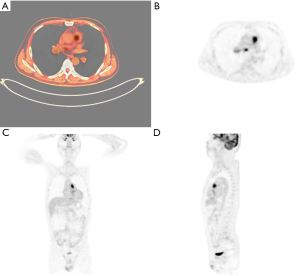

A 53-year-old man presented with exertional dyspnea and chest pain over 6 months, and suddenly developed hemoptysis 10 days ago. Contrast-enhanced computed tomography (CT) showed three filling defects in the main pulmonary artery, right pulmonary artery trunk and branch (Figure 1). Significant enhancement can be seen in the filling defects which grows along the vessel wall while the small vessel has no obvious embolism. Echocardiography performed that the main and right pulmonary artery had three hypoechogenic areas, and the blood flow in pulmonary artery was obviously accelerated. There was no risk factor for embolism in patient, and no abnormality in d-dimer and lower extremity vascular ultrasonography. Pulmonary artery computed tomography angiography (CTA) showed chronic thrombosis in the main pulmonary artery, right pulmonary artery, and branch. The lesions are large and may involve lung tissue. The lesion faces the blood flow surface full, bulging, unlike the pulmonary embolism is always a cup-shape. The result of positron emission tomography-computed tomography (PET-CT) is positive. It is performed that the size of the main pulmonary artery lesion was about 26 mm × 23 mm, the standardized uptake value maximum (SUVmax) value was 23.7, the lesion of the right pulmonary artery was about 14 mm × 20 mm, the SUVmax value was 11.3, the lesion size of the right pulmonary artery branch was about 16 mm × 20 mm, and the SUVmax value was 6.4 (Figure 2). PET is associated with abnormal increase in local glucose metabolism, therefore is considered as a primary malignant tumor of the pulmonary artery. The final clinical diagnosis of this patient is pulmonary artery sarcoma which is a rare neoplasm that appears always similar to pulmonary thromboembolism.